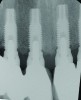

Fig 1 through Fig 6. Periapical radiographs of a 52-year-old man who received a fixed porcelain-fused-to-metal reconstruction supported by abutments attached to externally hexed dental implants. Fig 1 through Fig 3 are at initial prosthesis placement: maxillary right (Fig 1), textured surfaced threaded titanium implants at site Nos. 2, 4, and 6; maxillary anterior (Fig 2), implants at site Nos. 7 through 9; maxillary left (Fig 3), implants at site Nos. 12 and 14. Fig 4 through Fig 6 are 10 years post-insertion of the prosthesis: maxillary right (Fig 4), maxillary anterior (Fig 5), and maxillary left (Fig 6). Note minimal to no bone loss radiographically around the implants 10 years post-insertion of prosthesis.

Figure 1